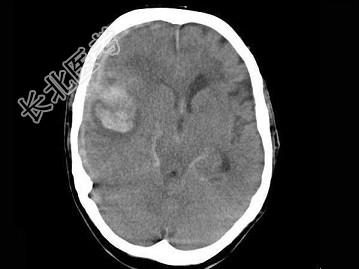

- 单项选择题女,79岁, 步行时突然摔倒,结合图像, 最可能的诊断是 ( )

A、右大脑中动脉破裂出血

B、脑转移瘤出血

C、脑膜炎

D、脑梗死

E、脑脓肿